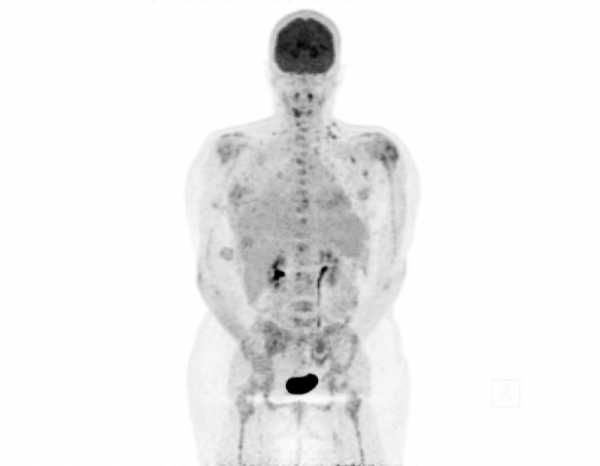

A cette occasion, l’Institut national du cancer (Inca) a rendu public son rapport annuel sur les cancers en France. Outre des données générales, un focus y est fait sur le cancer du sein et sur le tabac, facteur de risque responsable de 44 000 décès en France. Le rapport note que, pour promouvoir le sevrage tabagique des patients, « il serait important que la prévalence tabagique des professionnels de santé français rejoigne celle de leurs homologues américains et anglais, autour de 5 % ».

Le Groupe des Centres de lutte contre le cancer Unicancer, de son côté, met en avant la chirurgie ambulatoire et les thérapies ciblées, appelées à prendre une importance majeure dans les années à venir. La liste des manifestations prévues aujourd’hui est disponible sur son site.

- Cancers féminins : des voies de traitements prometteuses